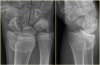

손목 성장판 골단판 골절(Epiphysiolysis fracture)

X-ray : 손목 성장판 골단판 골절(Epiphysiolysis fracture)